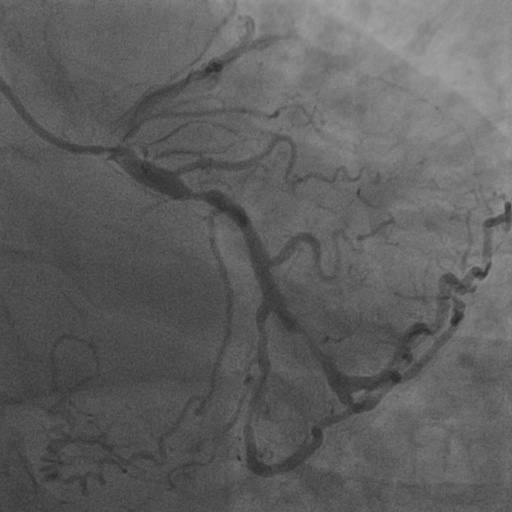

4.1 XACV Dataset

We collect 111 complete records of coronary artery X-ray videos from 59 patients, encompassing the injection, flow through the blood vessels around the heart, and dissipation of the contrast agent. Subsequently, we establish the XACV (X-ray Angiography Coronary Video) dataset. Each video consists of an average of 86 frames of high-resolution coronary artery X-ray images, with an equal distribution of left and right coronary arteries. We invite experienced radiologists to annotate the vascular regions, focusing on one or two frames where the contrast agent is most prominent in each video. These annotations are used only for evaluation in our method, not for training, maintaining the unsupervised nature of our approach. The data collection protocol involves several key steps, including patient preparation with informed consent and metal object removal, image capture using a Philips Allura Xper FD20 machine for standardized frontal (PA) and lateral views, DICOM file storage, and de-identification for patient privacy. Experienced radiologists perform diagnostic annotations using standardized tools and methods, with multiple annotations to enhance accuracy. Quality control measures, secure data management, and strict adherence to ethical guidelines and privacy regulations are implemented throughout the process. The XCAD dataset contains only a single image, and the CADICA video dataset does not provide corresponding ground truth. Therefore, in the following experiments, we conduct all the analyses on our collected XACV dataset and the corresponding GT for each sequence. In Figure 5, we show that compared to other publicly available datasets, XCAD (Ma et al., 2021) and CADICA (Jiménez-Partinen et al., 2024), our dataset exhibits finer annotations in the vascular regions, providing an advantage for future related tasks. The development and use of our dataset have been approved by our institution’s IRB. We will make the XACV dataset publicly available.